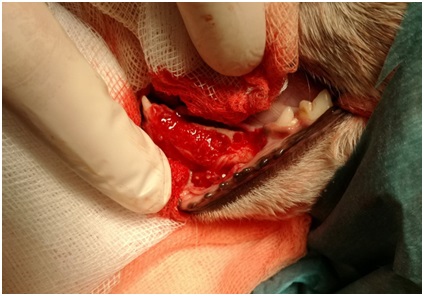

Po odpreparování sliznice vidíme místo, kde je místo zubu cysta. Zasahuje až ke kořeni špičáku.

8.jpg

Celá dutina se vyplnila kostním granulátem.

10.jpg

Celé místo se překrylo a přešilo odpreparovanou sliznicí. Stejný postup se aplikoval i na druhé straně spodní čelisti, kde se cysta nacházela také.